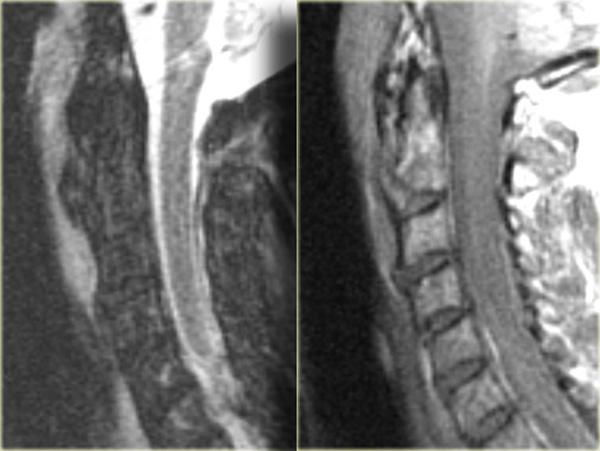

Có hai loại tổn thương tủy sống:

- Không xuất huyết, chỉ biểu hiện tăng tín hiệu trên MRI do phù nề.

- Xuất huyết với các vùng giảm tín hiệu nằm trong vùng phù nề.

Có mối tương quan chặt chẽ giữa chiều dài vùng phù nề tủy sống và kết cục lâm sàng.

Tuy nhiên, yếu tố quan trọng nhất là có hay không có xuất huyết, vì tổn thương tủy sống xuất huyết có tiên lượng cực kỳ xấu.

Tổn thương tủy sống trung tâm ở bệnh nhân chấn thương tăng duỗi trên nền thoái hóa và hẹp ống sống có sẵn.